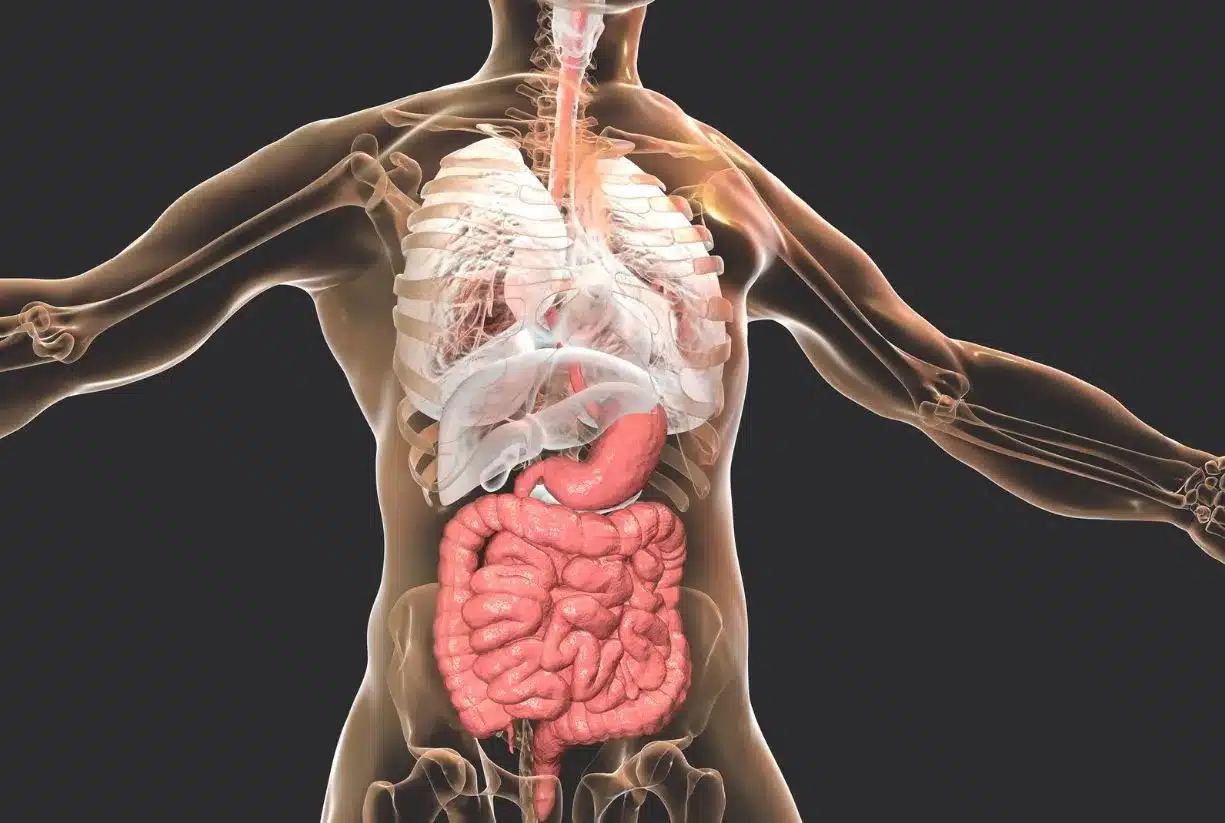

Ο γαστρεντερικός σωλήνας, που περιλαμβάνει το στομάχι, τα έντερα και τα συναφή όργανα, παίζει καθοριστικό ρόλο στη συνολική υγεία και ευεξία μας. Είναι υπεύθυνος για την πέψη της τροφής, την απορρόφηση των βασικών θρεπτικών συστατικών και λειτουργεί ως κρίσιμο φράγμα έναντι των βλαβερών ουσιών.